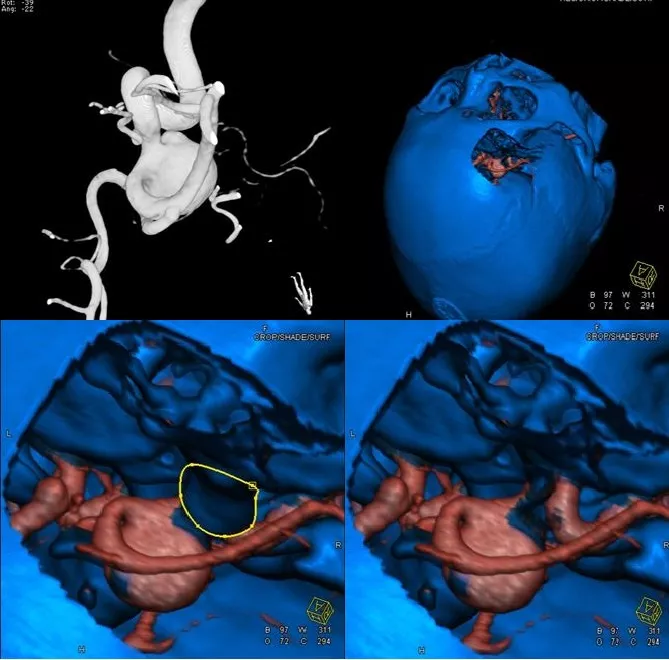

入院后完善CTA,DSA等检查提示颅内多发动脉瘤:

其中右侧颈内动脉眼段动脉瘤(约13.8*14mm大小,瘤颈8.04mm)。和家属沟通病情,告知介入和开颅手术两种治疗方式的风险利弊后,患者家属选择开颅右侧眼动脉段动脉瘤夹闭手术治疗。

进一步行DSA+CT融合,模拟手术入路视角。

手术采取复合手术条件下磨除前床突,利用Scepter球囊封堵瘤颈,阻断瘤内供血后行动脉瘤夹闭。